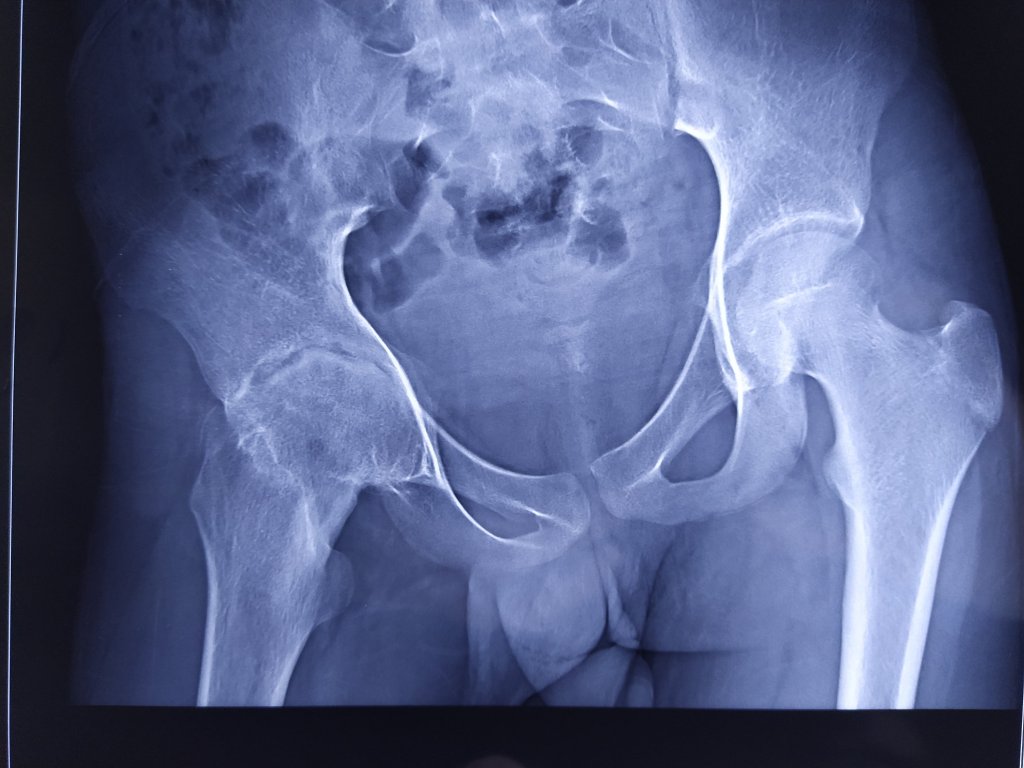

Tuberculosis of a Joint

Tuberculosis can infect any joint and bone or spine.

Symptoms would be pain, fever, swelling and difficulty using the joint. If not treated early the joint is completely destroyed by the bacteria and the inflammation caused. Pus accumulates in the joint and joint movements become very much reduced. There will be pain and severe stiffness of the joint.

It is very important to identify Tuberculosis infection in bone and joint and to treat it early.

This is especially true if major joints like Hip, Knee and Spine.

The doctor may prescribe blood tests, scans like MRI if needed and X-rays if there is suspicion of TB.

The treatment includes medical care with anti Tuberculosis medications, rest, exercise and surgical treatment of there is dislocation or destruction of the joint.